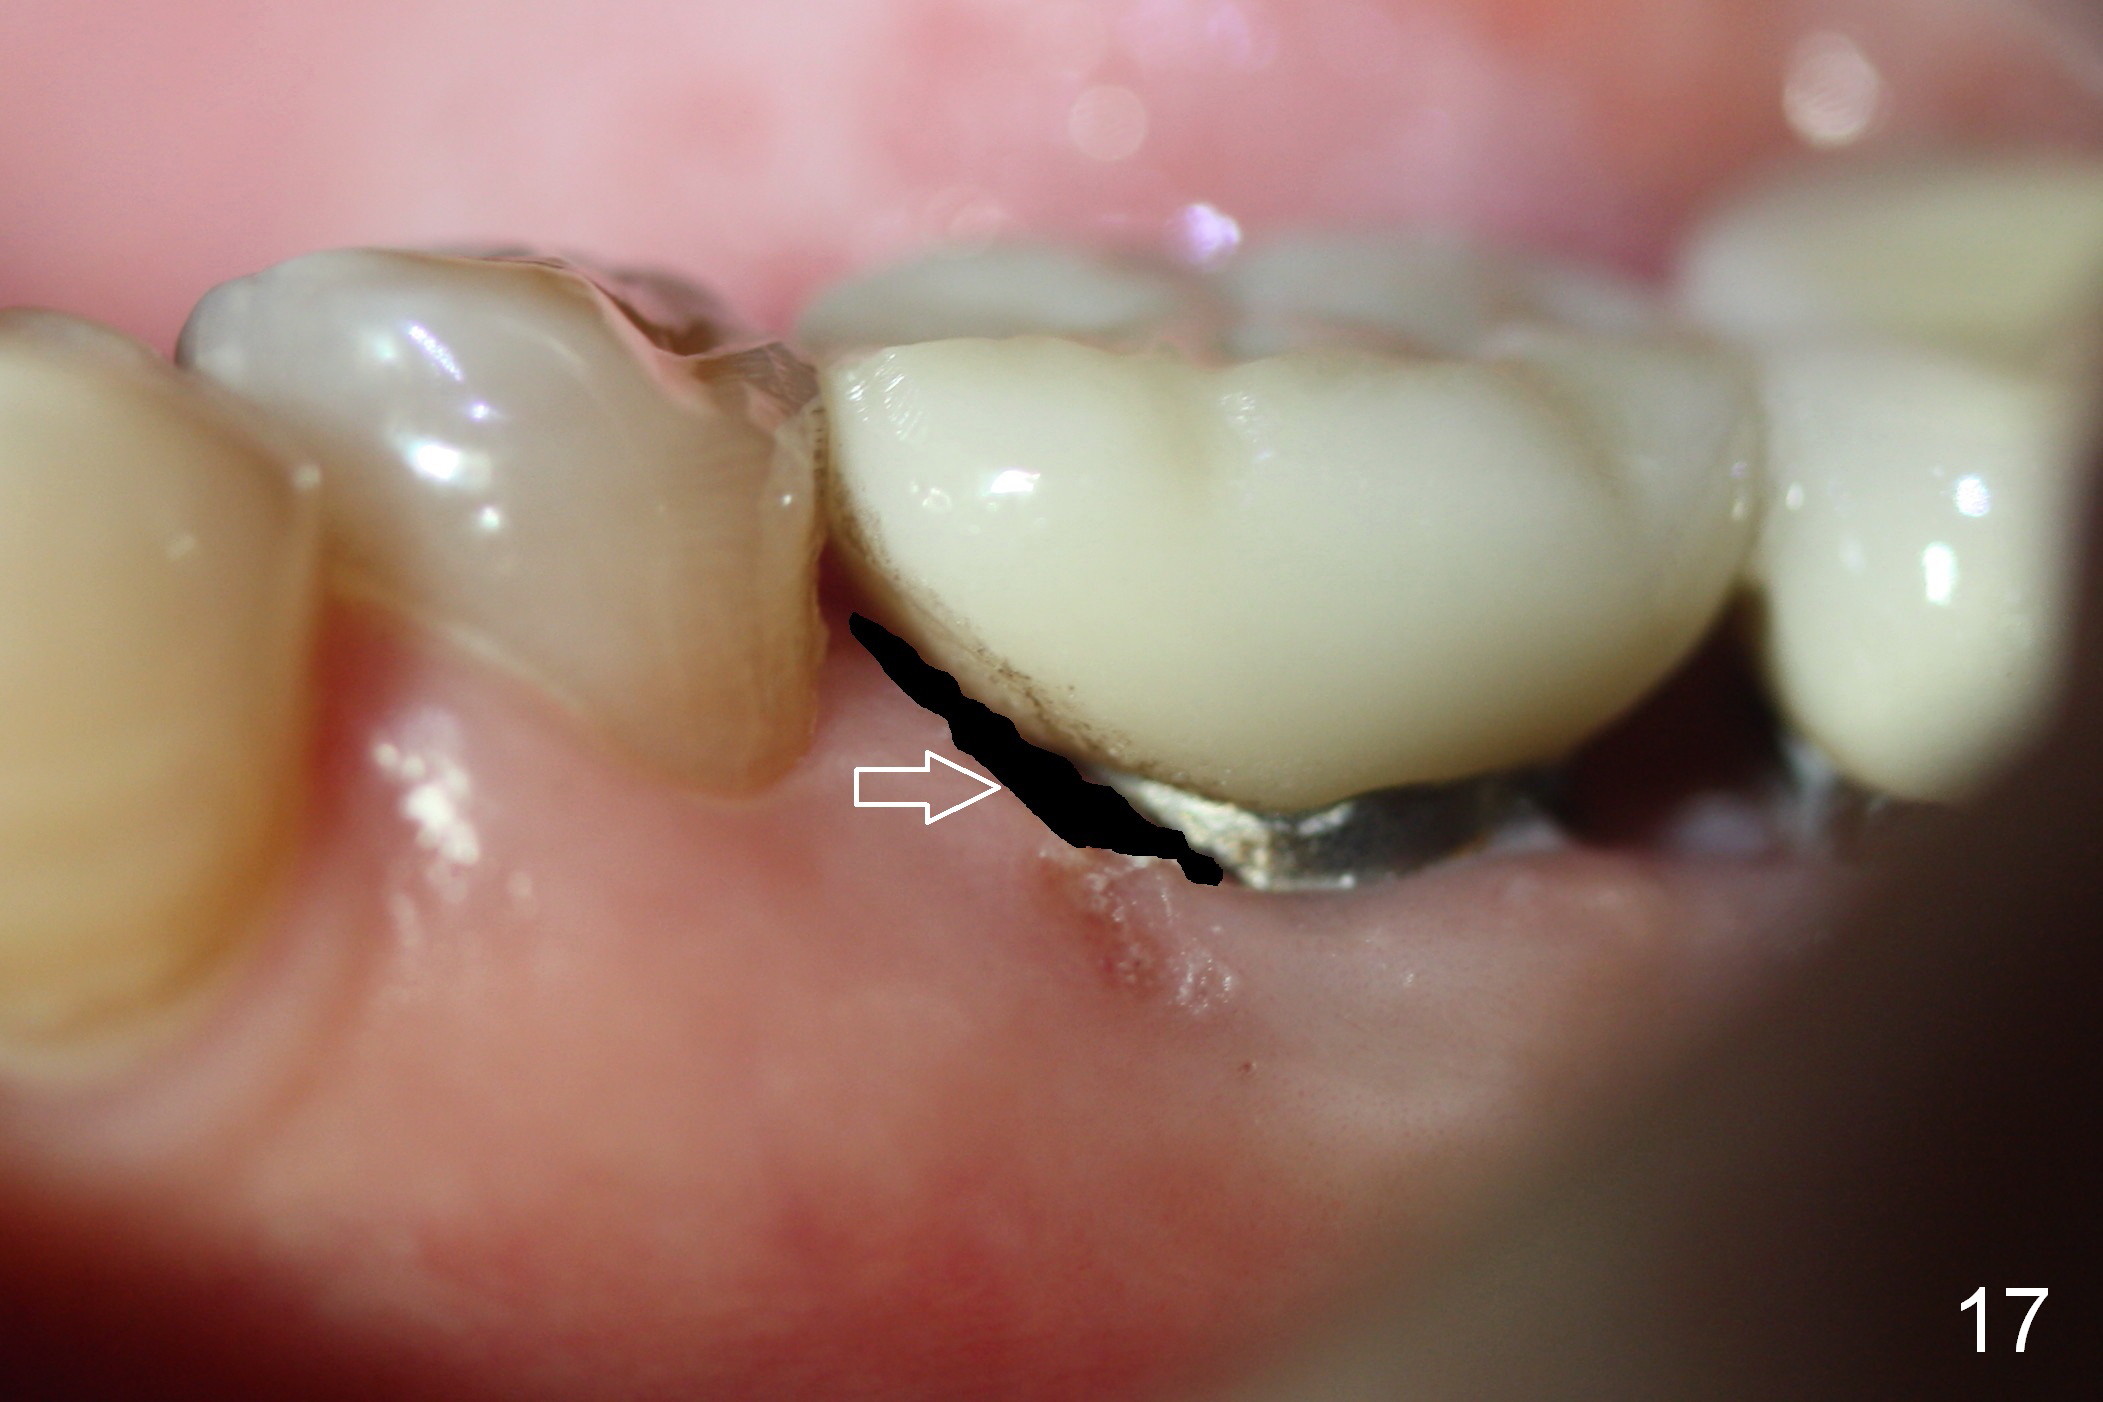

After removing the crown, the margin is lowered clinically. In the lab, the mesial gingiva in the model is to be trimmed ~1 mm (Fig.17 arrow (black area)) so that the mesial embrasure is closed as much as possible (Fig.18). The contact area is larger both buccolingually and apicocoronally. Clinically, the mesial margin of the temporary crown should be a little bit bulging to push the mesial papilla mesially so that there is enough space to clean cement for the permanent crown.